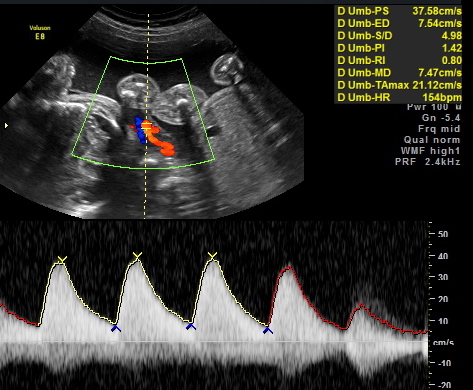

Friday we surpassed yet another milestone! The babies have been cooking for 7 months, which means we are now above the average gestational age for quintuplets. All of the babies were measured on Friday and they are all measuring within a day or two of the recommended size for babies at this point in pregnancy.

All of their organs (kidneys, bladders, hearts, brains, stomachs) look great and are also appropriate sizes. The blood flow to Elle has improved and has stabilized. All heart rates remain within normal limits, and are often on the higher side, which is probably because they just can’t sit still. We are truly excited to meet our little wiggle worms!